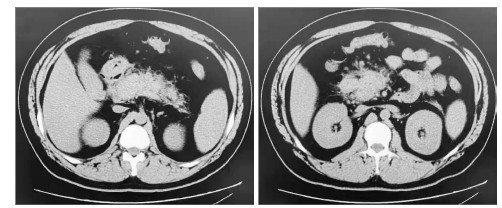

病情演变:患者病情进展快,入院时已有消化、循环、神经等多系统症状。诊疗重点:鉴别急腹症、心肺系统急症的不典型表现。入院后予以心电监护、胃肠减压、液体复苏,紧急完善相关实验室检查。血常规:白细胞14.14×109/L,中性细胞87.20%,中性粒细胞12.33×109/L。尿常规:隐血1+,蛋白2+,糖4+,酮体3+。血气分析:pH 7.15,PCO2 34 mmHg,PO2 75 mmHg,乳酸2.7 mmol/L,HCO3- 27.2 mmol/L;血糖18.7 mmol/L;Ca2+ 1.18 mmol/L,K+ 2.4 mmol/L。降钙素原1.1 ng/mL。肌钙蛋白I、肌酸激酶同工酶、N末端脑钠肽前体、肝肾功能检查均阴性。血尿淀粉酶轻度升高。凝血功能:纤维蛋白原739 mg/dL,D二聚体13 500 ng/mL,乳糜血。甘油三酯(triglyceride, TG)17.98 mmol/L。心电图:窦性心动过速,电轴左偏,心率130次/min。心脏、腹部超声:(1)心内结构大致正常,室壁运动正常;(2)胸腔少量积液;(3)胰腺体积大,回声不均,肝周积液。胸部、腹部CT(图 1):(1)两肺下叶炎症;(2)胸腔少量积液;(3)脂肪肝;(4)急性胰腺炎。

左图为胰尾渗出、肿胀;右图为胰头肿大,胰腺棉絮样渗出,肝区积液 图 1 患者入院时上腹部CT

依据患者腹痛、急性胰腺炎影像、乳糜血、TG > 11.30mmol/L、排除占位和结石等其他病因并参考Balthazar CT分级,疾病诊断:HTG-AP(中度重型)、糖尿病酮症酸中毒、肺部感染、低钾血症。因存在有效循环血容量不足、胰性脑病等表现,病情重,遂收住EICU。